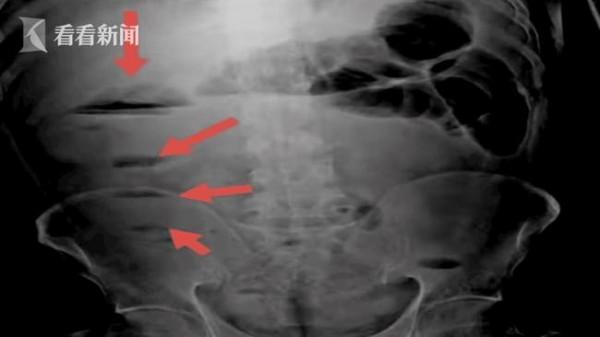

陳爹爹稱,在網上看到油可以潤滑,就找了一些油水足的排骨湯、鴨湯去喝,結果喝了一段時間肚子開始疼起來了,到醫院一檢查,突發腸梗阻。

油脂不是能潤滑嗎,吃下去怎麼會出現腸梗阻呢?醫生介紹,老年人的身體新陳代謝緩慢,消化功能退化,如果不注意飲食結構,更容易出現消化不良。久而久之的話長期排不出來的話,就形成了這種糞石阻塞了我們的腸腔,形成了一個腸梗阻的情況。